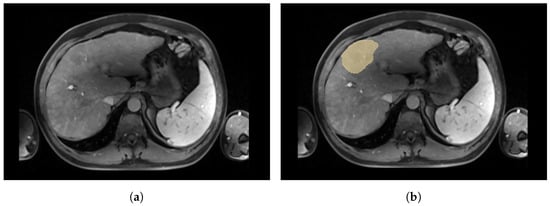

The annotator used delineation tools available on the MIM SurePlan LiverY90 software [23] to segment both the liver and tumours. Brushes and pencil tools were used indistinctly. For the liver segmentation, the whole liver was considered; extra-hepatic arteries and gallbladder were excluded. For the tumour segmentation, all tumours were considered (if more than one was present). In practice, the expert in charge of the manual segmentation separates the tumour and necrosis because the volume occupied by necrosis should not be taken into account in the value of the tumour burden used for dosimetry calculation. However, as only a few cases showed necrosis, we decided not to include the necrosis label in the dataset. Thus, necrosis has been classified as tumour if located within the tumour and as liver otherwise. Figure 2 shows necrosis within the tumour.

Figure 2.

Axial slice of a CE-MRI from a patient with necrosis within the tumour. (a) Axial slice of a CE-MRI from patient with necrosis. (b) Axial slice of a CE-MRI from patient with tumour labels. (c) Axial slice of a CE-MRI from patient with necrosis labels. On (b,c), respectively representing the tumour in yellow and the necrosis in red, necrosis is located in the centre of the tumour. In this case, necrosis is therefore classified as tumour in our dataset.